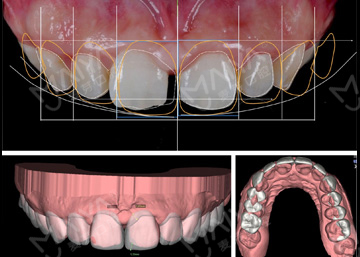

数字化精确导航种植

导航辅助种牙,创口小更舒服

• >智能导航,精确高效

• >适用症广,缺牙重生

• >避免盲种,成功率高

• >种牙精准,不伤神经